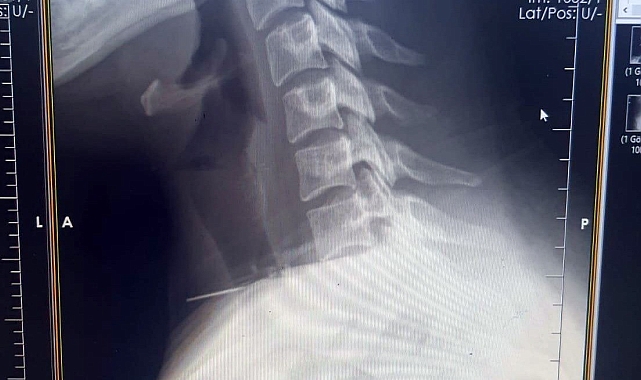

Edinilen bilgiye göre olay, Şanlıurfa'nın Birecik ilçesinde yaşandı. Boğazına dikiş iğnesi saplanan 25 yaşındaki Z.İ., Birecik Devlet Hastanesine başvurdu. Radyolojik incelemeler ve klinik değerlendirmeler sonucunda, 3 santimetrelik iğnenin boğaz bölgesinin derinliklerine doğru ilerlediği tespit edildi. İğne, yaklaşık 1 saat süren ameliyatla çıkarıldı. Ameliyat sonrası süreci sorunsuz atlatan hasta taburcu edildi.

Ameliyatı gerçekleştiren Birecik Devlet Hastanesi Kulak Burun Boğaz ve Baş Boyun Cerrahisi Uzmanı Dr. Rafet Yıldırım, boynuna iğne saplanan kadın hastayı başarılı bir operasyonla sağlığına kavuşturduklarını söyledi.